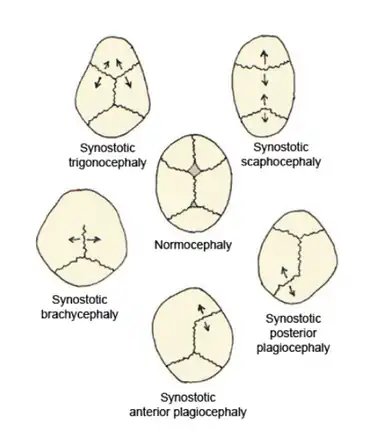

Trigonocephaly is a congenital condition due to premature fusion of the metopic suture (from Ancient Greek metopon 'forehead'), leading to a triangular forehead. The premature merging of the two frontal bones leads to transverse growth restriction and parallel growth expansion. It may occur as one component of a syndrome together with other abnormalities, or in isolated form. The term is from Ancient Greek trigonon 'triangle' and kephale 'head'.

Diagnosis can be characterized by typical facial and cranial deformities.[2][19]

Observatory signs of trigonocephaly are:

- a triangular forehead seen from top view leading to a smaller anterior cranial fossa

- a normal cephalic index (maximum cranium width / maximum cranium length) however, there is bitemporal shortening and biparietal broadening